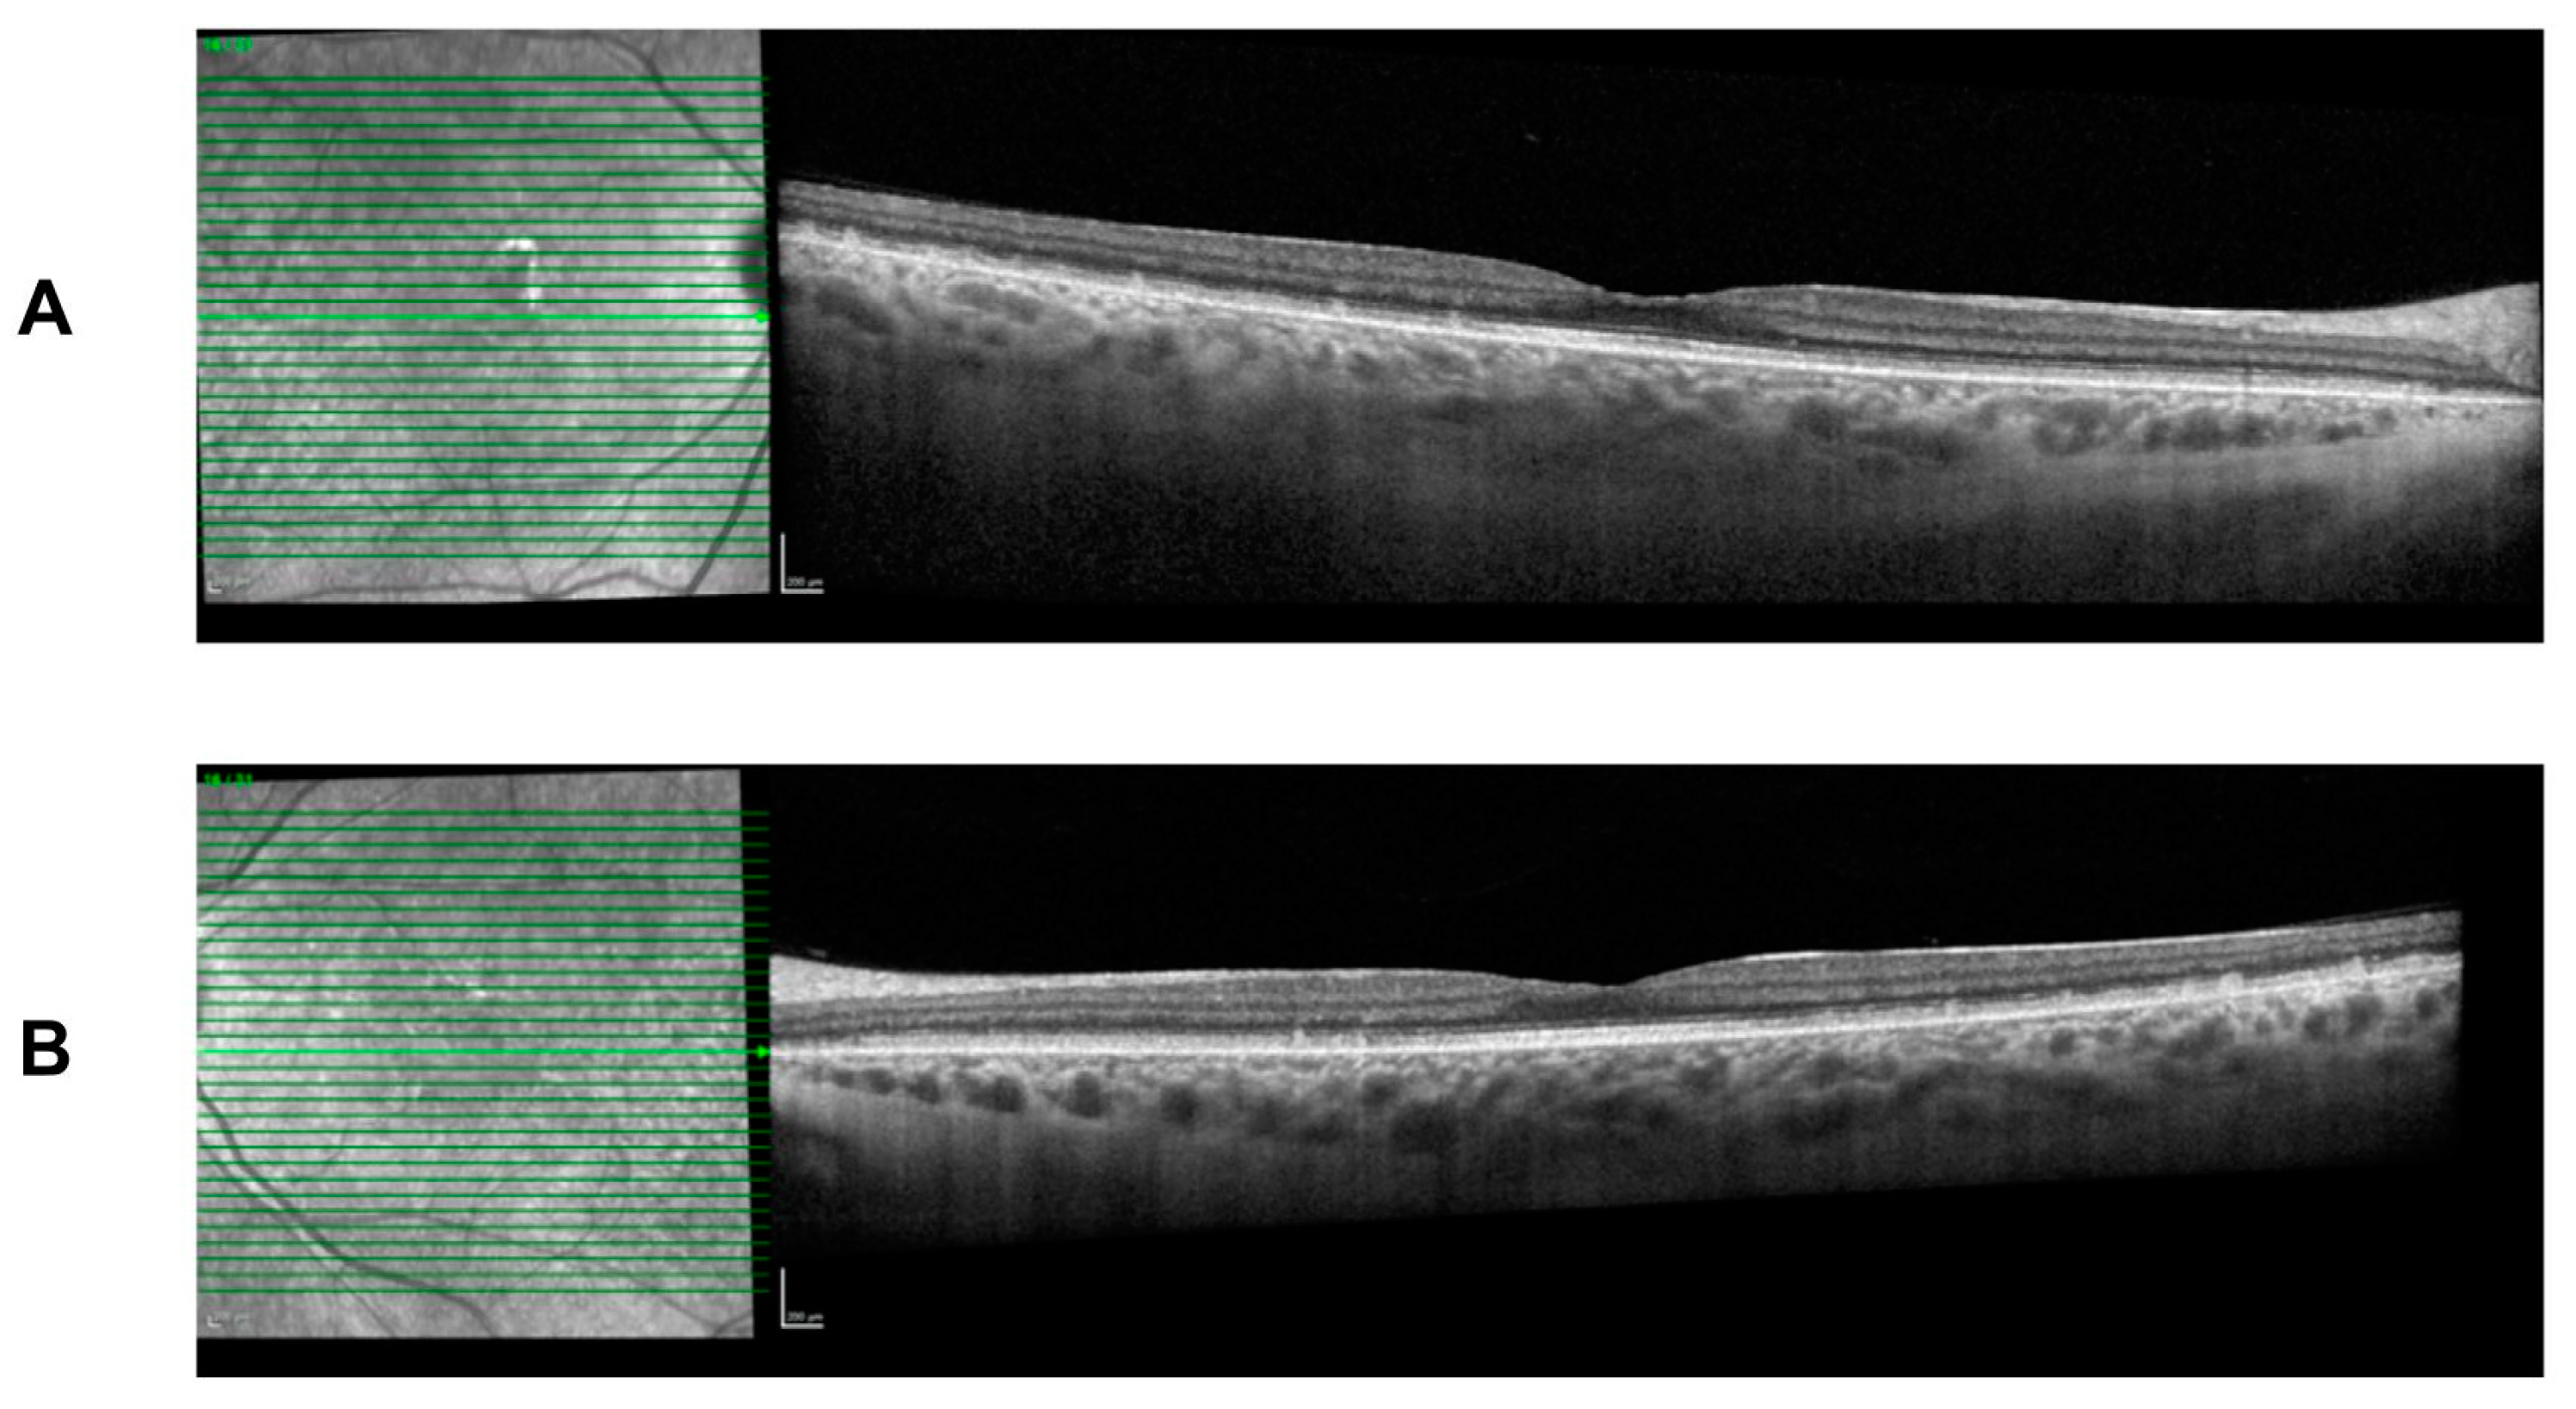

She continues to present with the typical FAP phenotype of small subretinal white dots 360 degrees throughout the fundus, particularly in the mid-periphery with fundoscopy and retinal imaging (Figure 4). The white dots spare the fovea region and preserve her visual acuity. Spectral-domain optical coherence tomography (SD-OCT) imaging is stable over time and shows the presence of subretinal deposits, attenuated ellipsoid zones, and a thick choroid in both eyes (Figure 5).

Figure 5.

Spectral-domain optical coherence tomography (SD-OCT) at age 26 with deep retinal deposits that are fovea sparing. There is mild attenuation of the ellipsoid zone and a thick choroid. Findings are symmetrical in both eyes. (A) Right eye. (B) Left eye.

Throughout follow-up assessments and imaging, the natural history and progression of the patient’s FAP has shown a stable clinical phenotype. Nyctalopia and light vision deficits have subjectively remained stable with delayed dark adaptation. The patient’s best-corrected visual acuity continues to remain stable over 7 years; however, the patient’s color vision assessments indicate there may have been a progression of color vision deficits between the ages of 5 and 21. OCT imaging has remained stable over time, showing a lack of fovea involvement and little impact on central vision.